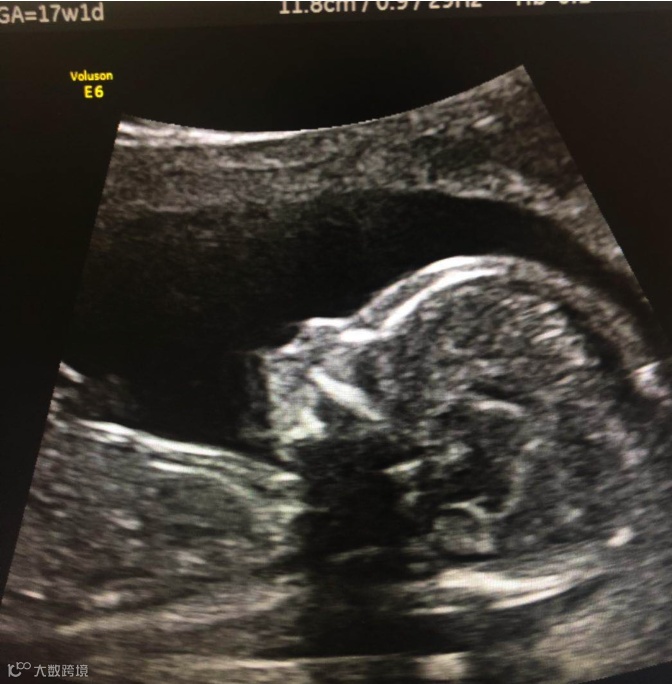

孕17周超声复查,小下颌胎儿仍表现为小下颌,同时出现生长受限,头围及腹围位于-2SD(标准差),长骨明显短于正常,股骨长度< -4SD。

(Astraia软件)